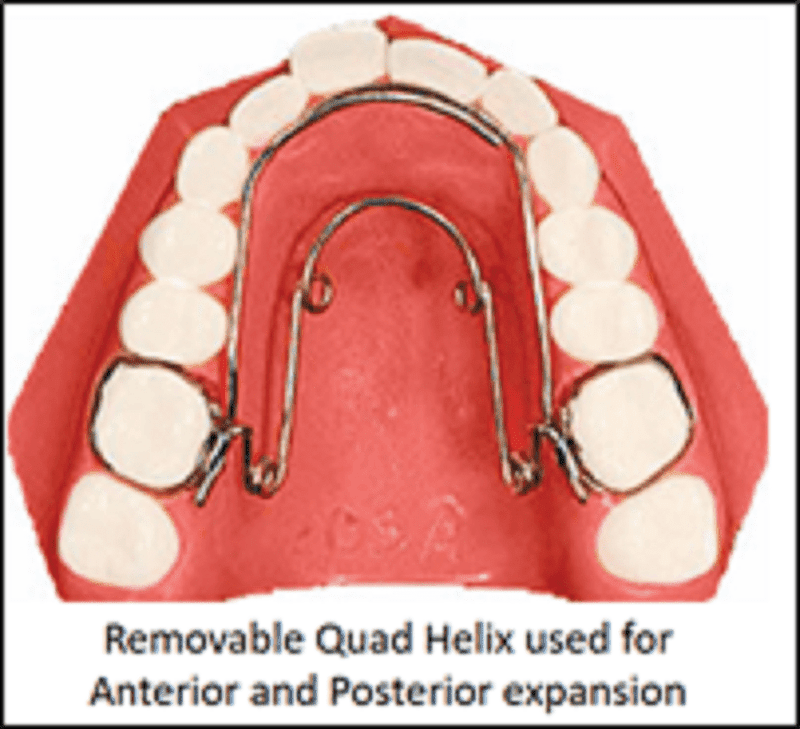

c) Removable quad helix appliances

Removable quad helix is inserted into the lingual attachment (lingual sheath) which is welded or soldered to the molar band. This permits adjustment of the appliance outside the mouth.

Quad/ Tri/Bi Helix appliance

Quad helix was introduced by Robert M Ricketts.

The appliance is a precursor to the tri- and the bi-helix appliances. They are all named after the number of helices incorporated in the appliance.

Appliance framework ̶ The quad helix consists of four helices made of 0.038″ diameter wire (elgiloy or stainless steel wire), soldered to the molar bands. The length of wire increases the range of action and flexibility, and decreases the force levels. The tri- and the bi-helix appliances incorporate only three and two helices respectively.

It is a fixed appliance comprising stainless steel bands cemented onto the maxillary first molars and a standard stainless steel arch attached to the palatal surfaces of the teeth.

Parts of quad helix: (A) posterior helix, (B) palatal bridge, (C) anterior helix, (D) anterior bridge and (E) outer arm.

The quad-helix consists of two anterior and two posterior helices. The portion of wire in between the two anterior helices is called the anterior bridge and that connecting the anterior helices and the posterior helices is called the palatal bridge. The free ends that are usually adapted close to the premolar teeth are called the outer arms. The outer arms are soldered to the molar bands. The posterior helix should not extend more than 2 mm distal to the first permanent molar.

Activation – The appliance is capable of producing differential expansion i.e. it can be activated to produce expansion levels in the premolar and molar regions.

It can be activated prior to cementation of the bands by stretching the molar bands apart or in the mouth with the use of three-prong pliers.

- In the anterior bridge: Results in expansion in the molar region

- In the palatal bridge: Derotation and expansion of molar on the same side and distalization of molar on the opposite side

- Outer arms are activated to expand canines and premolars

- Opening of posterior helix expands the buccal arm

An initial expansion of 8 mm will produce 14 oz of force. Average force is 200–400 g depending upon the amount of expansion or activation. The expansion of the steel arch (normally 10 mm before insertion) exerts a lateral force on the teeth, resulting in a predominant transverse dentoalveolar expansion of the maxillary arch. If necessary, the appliance can be reactivated after 6 weeks. Once inserted, the appliance is not dependent on patient compliance.

Indications of quad helix appliance

- Narrow upper arch that needs expansion, e.g. in crossbites

- Crowded, mixed or permanent dentition in which long range growth can be predicted and requires mild expansion as there is lack of space for the upper laterals

- Class II malocclusions where the upper arch needs effective widening and upper molars need distal rotation

- Class III malocclusions where the upper arch needs effective widening and advances with class III elastics

- Thumb sucking and tongue thrusting cases with their modifications

- Unilateral or bilateral cleft palate

Advantages

- It provides excellent expansion in cleft palate patients

- Expansion is smooth and controlled

- In young children, skeletal expansion can be achieved

- Anterior bridge with helices acts as reminder for habit breaking

For correction of unilateral posterior crossbite in mixed dentition, it has been proved that the Quad Helix appliance is superior to the expansion plate in terms of effectiveness and cost minimisation and is therefore the preferred method of treatment (Petrén et al., 2013).

Disadvantages

- One major disadvantage of this appliance is buccal tipping of molars during excessive activation. This can be prevented by torquing the roots buccally.